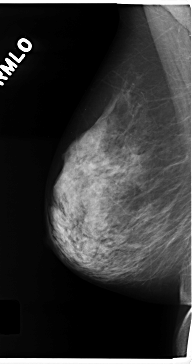

C_0175_1.RIGHT_MLO

RIGHT_CC LINES 4704 PIXELS_PER_LINE 2600 BITS_PER_PIXEL 12 RESOLUTION 50 NON_OVERLAY

RIGHT_MLO LINES 4720 PIXELS_PER_LINE 2496 BITS_PER_PIXEL 12 RESOLUTION 50 NON_OVERLAY